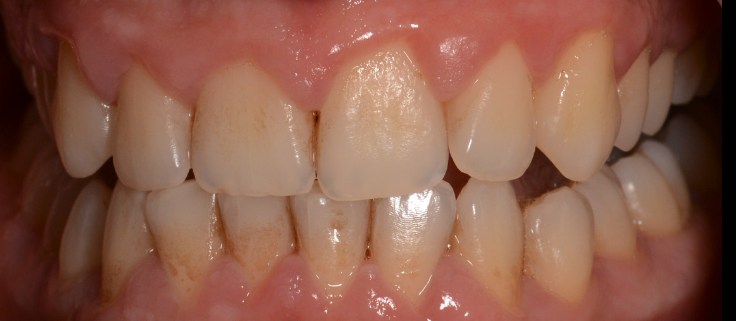

Mulți pacienți tind să amâne vizita la medic, pentru că de cele mai multe ori nu este prezentă senzația dureroasă. Placa bacteriană greu accesibilă și mai ales tartrul pot fi îndepărtate printr-un simplu detartraj cu ultrasunete și un periaj dentar profesional efectuate o dată la 6 luni de către medicul dentist. Spațiile mai greu accesibile cu tartru aderent se vor igieniza mecanic cu instrumente speciale de detartraj: chiurete parodontale și scalare. Prin îndepărtarea plăcii bacteriene și a tartrului și prin menținerea unei igiene corecte, semnele de afectare gingivală vor dispărea, iar gingia își va recăpăta starea de sănătate inițială. Gingivita simplă netratată va evolua în anumite zone ale cavității orale spre boala parodontală. Netratată, aceasta se va extinde treptat la tot mai mulți dinți, având o evoluție cronică și într-un final, după distrucții extinse, se vor pierde dinții. Tratamentul bolii parodontale este mult mai complicat și mai laborios decât al unei gingivite simple, de aceea este foarte important să se intervină în stadii cât mai incipiente ale bolii. (Fig. 5.1.5, 5.1.6, 5.1.7)